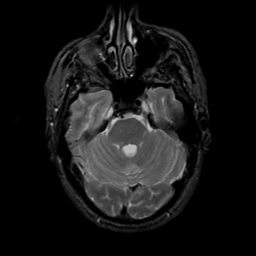

MR Study #10, April 28, 1991 -- Slice #14